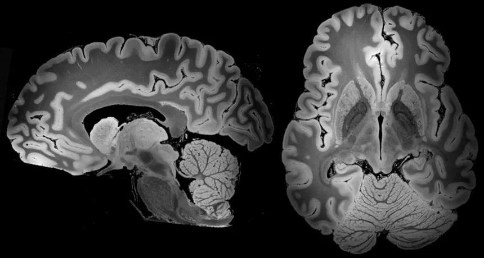

神外前沿讯,据美国《科学新闻》网站(sciencenews.org)7月8日报道,经过超过100小时的扫描,美国的研究人员,获得了迄今为止较为详细的整个人类大脑的三维图像。通过强大的7T磁共振(MRI),新图像的分辨率可以清晰呈现直径小于0.1毫米的物体。

扫描显示出杏仁体等大脑构造的生动细节,可以更深入地了解结构的细微变化与创伤后应激障碍等疾病之间的关系。

7T功能强大、扫描时间长以及大脑处于高度静止状态,这些因素导致生成的图像分辨率极高。

Over 100 hours of scanning has yielded a 3-D picture of the whole human brain that’s more detailed than ever before. The new view, enabled by a powerful MRI, has the resolution potentially to spot objects that are smaller than 0.1 millimeters wide.

The scan shows brain structures such as the amygdala in vivid detail, a picture that might lead to a deeper understanding of how subtle changes in anatomy could relate to disorders such as post-traumatic stress disorder.

Before the scan began, researchers built a custom spheroid case of urethane that held the brain still and allowed interfering air bubbles to escape. Sturdily encased, the brain then went into a powerful MRI machine called a 7 Tesla, or 7T, and stayed there for almost five days of scanning.

The strength of the 7T, the length of the scanning time and the fact that the brain was perfectly still led to the high-resolution images, which are described May 31 at bioRxiv.org. Associated videos of the brain, as well as the underlying dataset, are publicly available.

Researchers can’t get the same kind of resolution on brains of living people. For starters, people couldn’t tolerate a 100-hour scan. And even tiny movements, such as those that come from breathing and blood flow, would blur the images.